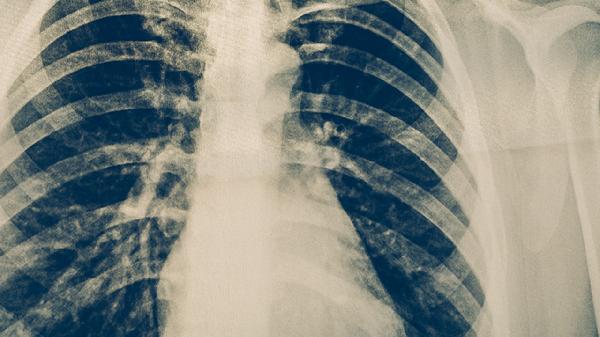

肺结核胸部X线常见斑片状阴影、空洞形成和钙化灶,病变多呈多形性改变。肺癌影像学表现为团块状阴影,边缘可有分叶或毛刺,可能伴随肺不张或胸腔积液。增强CT中肺结核病灶强化不明显,肺癌多呈明显强化。